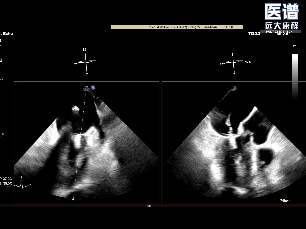

TEE

TEE-2D血流

术中完成房间隔穿刺后,将可操控导引导管(SGC)及二尖瓣夹输送系统成功送入左心房。随后将瓣膜夹调整至二尖瓣上并逐步移至病变区域,经轴向调整后,夹合器于A1/P1交界区顺利捕获瓣叶并完成首次夹合,此时超声提示存在少量反流;为达到更优的治疗效果,王建安院士及刘先宝教授决定微调位置,打开夹合器调整轴向后,重新捕获瓣叶以夹合瓣叶并成功释放,最终有效解决了反流及脱垂问题。释放后食道超声评估仅存在少量反流,平均跨瓣压3mmHg,圆满完成手术。

夹合瓣叶后评估

夹合器释放后评估

术后平均压差为3mmHg